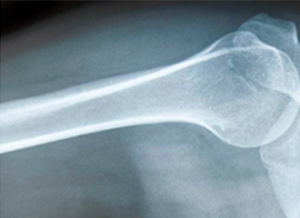

妈妈听完,笑了笑,耐心地解释道:“今天,妈妈就来给讲讲影像学的知识,然后你就知道X光、CT、MRI、B超的区别了。你说的‘拍片’,就是指X光检查。X光有很强的穿透能力,检查时就像给身体内部拍了一张平面影像的照片。当然,由于被照射的物体密度不均匀,拍摄之后,就会在底片上形成黑白不一的颜色。”

明明追问道:“骨头是不是白色的呢?”妈妈回答道:“对,所以骨折或者骨质增生的辅助检查,首选X光。”